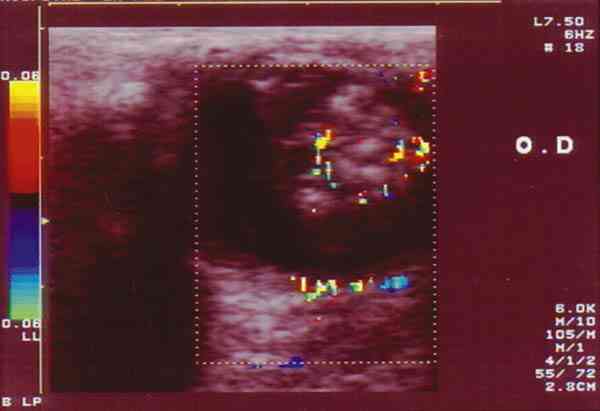

Figura 7. RB con extensa calcificación. Doppler color: registro

arterial en área no calcificada.